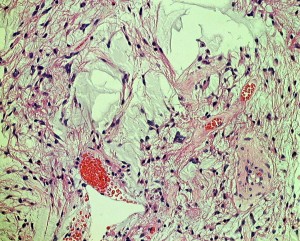

生後6ヶ月の視神経交叉腫瘍です。左では,monomorphous bipolar cellsとmucoid matrixが豊富に見られます。右では細い血管の周囲に腫瘍細胞が集簇するangiocentric patternが特徴的です。粘液性分が多くドロドロした腫瘍です。

3歳児例でのangiocentric patternで,乳児例より多少コンパクトになってきます。毛様粘液性星細胞腫においてもGFAP(右側)は強陽性です。